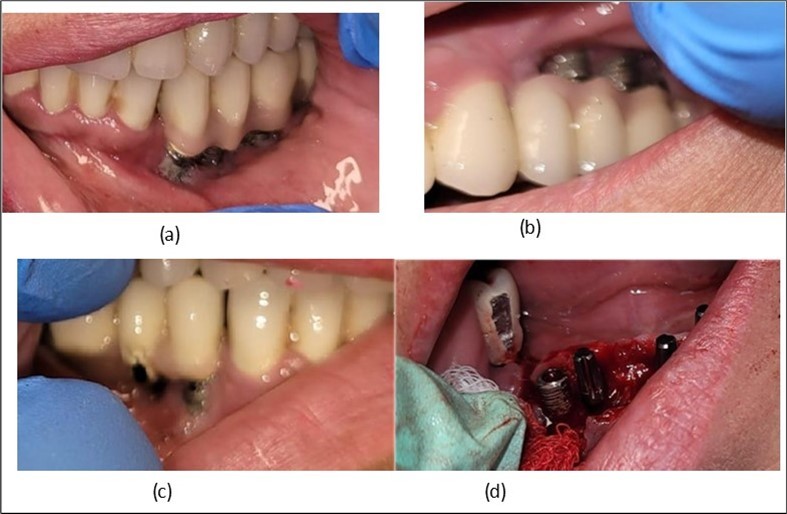

Clinically, we observe the exposure of the implants in the oral cavity with bacteria plaque on their surface, primarily due to the retentive surface of the implants. The exposure of the endosseous part of the two stage implants represents the starting point for mucositis and subsequently peri-implantitis (Figure 2). An important role is played by the occlusion of the prosthetic restorations and the way in which masticatory forces are transmitted to the implants. Prosthetic restorations with prominent vestibular cusps in contact with the opposing teeth, which during lateral movements lead to an increase in extrusive forces on the implant side (in this case, implants) (Figure 2a, b, c). A lingualized occlusion is preferred, where the masticatory forces are placed closer to the insertion axis of the implant.

Figure 2.Intraoral images of the exposed implants affected by peri-implantitis: (a) quadrant 3, vestibular view; (b) quadrant 2, vestibular view; (c) quadrant 4, vestibular view; (d) quadrant 4 after removal the prosthetic restoration and uncovering the implants, vestibulo-lingual view.